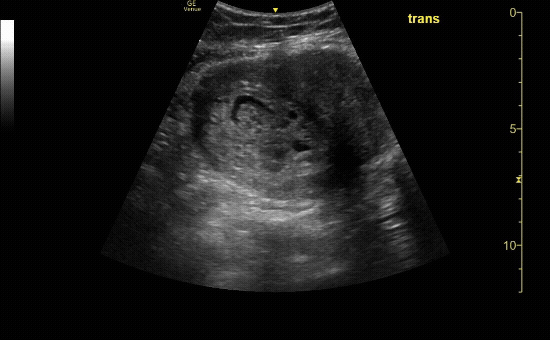

Transverse view of the uterus with no IUP and a left adnexal mass consistent with early ectopic pregnancy

c/o Victoria Gonzalez, MD